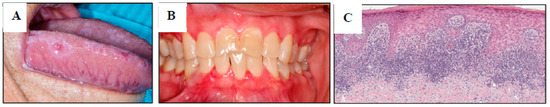

3.1. Clinical and Pathologic Features